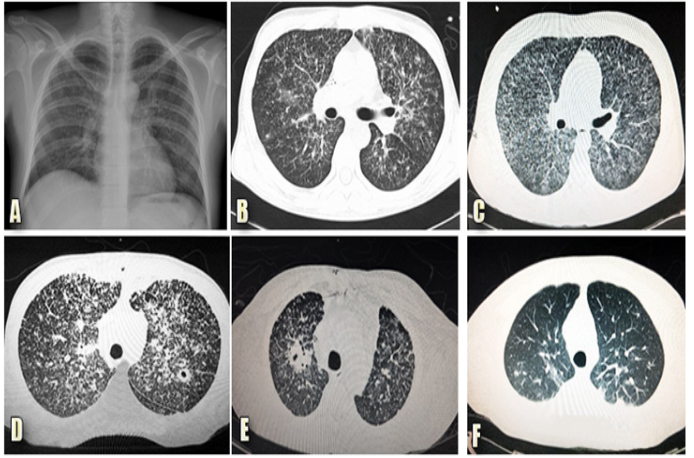

The most frequent tomographic sign was the presence of multiple nodular lesions, found in 39/61 patients (59%). Particularly, the pulmonary tomography of 2/61 patients (3%) reported no structural alteration (Figure 2).

Figure 2 Histoplasma capsulatum manifestations.

The series of images correspond to the following: A. Chest x-ray of an 18-year-old man, without comorbidities, who was exposed to an abandoned building, after which he developed dyspnea and intermittent fever; the image shows a reticulonodular pattern. B. High resolution computed tomography of the same patient; the image shows pleural thickening and random pulmonary nodules of varied sizes. C.High resolution computed tomography of a patient with: HIV infection; non-adherence to antiretroviral treatment; respiratory symptoms for 9 days; evening fever; dyspnea; dry cough; and diagnosed with disseminated histoplasmosis; the image shows randomized micronodules. D. High-resolution computed tomography of a patient with HIV and four months with symptoms; the image shows a pulmonary cavitary nodule. E. High resolution computed tomography of a 44-year-old man from Morelos state with a history of chronic consumption of immunosuppressive therapy; the image shows that there is a micronodular pattern in both lungs and a cavitated nodule in the upper right lobe of the lung. F. High resolution computed tomography of a patient with HIV with: few respiratory symptoms, hepatosplenomegaly, and diagnosed with disseminated histoplasmosis; the image shows some subpleural nodules in the left hemithorax.